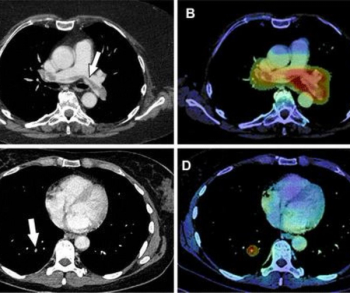

In a new study involving over 11,700 chest computed tomography (CT) scans in oncology patients, adjunctive artificial intelligence software demonstrated a sensitivity rate of 91.6 percent for incidental pulmonary embolism (IPE) and reduced median detection and notification time for IPE-positive scans from multiple days to one hour for a radiology department at a comprehensive cancer center.